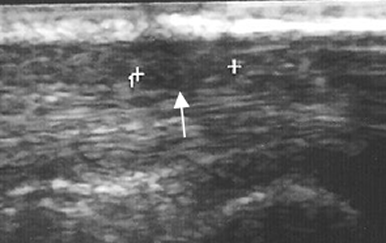

Fig 112 A. Fbromatosis.

Ecografia en corte sagital. Imagen ovalada, hipoecoica y parcialmente definida, en los tejidos blandos superficiales de la palma de la mano, por encima de los tendones flexores y compatible con fibromatosis.